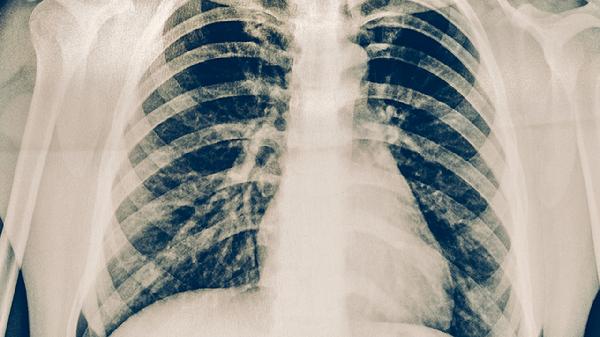

治疗期间每1-2个月需进行痰涂片检查、胸部X线或CT复查,评估病灶吸收情况。痰菌转阴后仍需完成至少6个月强化期治疗,防止复发。糖尿病患者、HIV感染者等高风险人群应增加随访频率,监测血糖和免疫功能变化,避免合并感染加重病情。